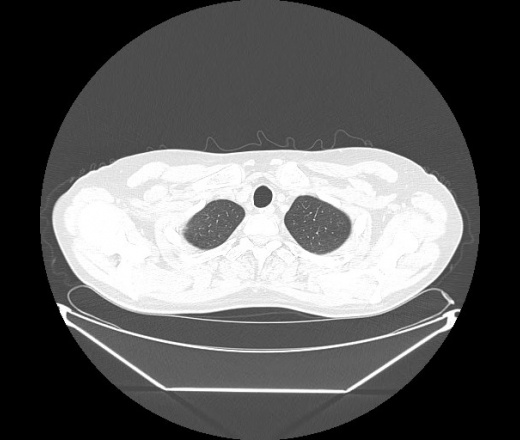

М. 1984 г.р.  Лихорадка 39, кашель , одышка.. и надоевший всем вопрос- "типично ли для ковид?" ( в настоящее время на него обязательно нужно дать ответ в своем протоколе)

На мой взгляд нетипично для ковид: много центрально-расположенных поражений, лобарное поражение нижней доли слева. 50/50

Не типичая картина для ковид.

КТ-признаки двусторонней бактериальной пневмонии.

Все верно, здесь абсолютно нетипичная картина, несмотря на матовое стекло с ретикулярными изменениями, но почему-то  посчитали иначе. Кстати,  "малыша" не заметили)?